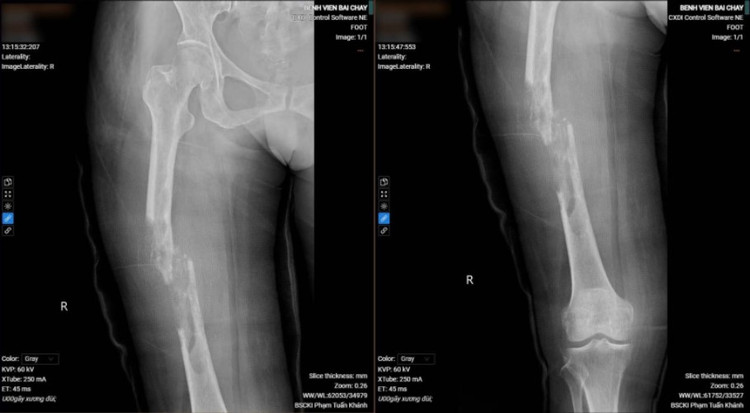

Bệnh nhân được xạ trị tích cực vùng não và xương đùi để tiêu diệt, ngăn chặn sự phát triển của tế bào ung thư, giảm đau, chống phù não. Tiếp đó, ca phẫu thuật phẫu thuật cắt bỏ đoạn u xương đùi do ung thư di căn, kết hợp xương, thay thế đoạn xương đùi khuyết bằng xi măng sinh học do bác sĩ Vũ Quang Nghĩa – Trưởng Khoa Chấn thương chỉnh hình thực hiện đã thành công giúp bệnh nhân phục hồi vận động.

![]() |

| Hình ảnh gãy xương, tiêu xương đùi phải của bệnh nhân trước và sau phẫu thuật - Ảnh BVCC |